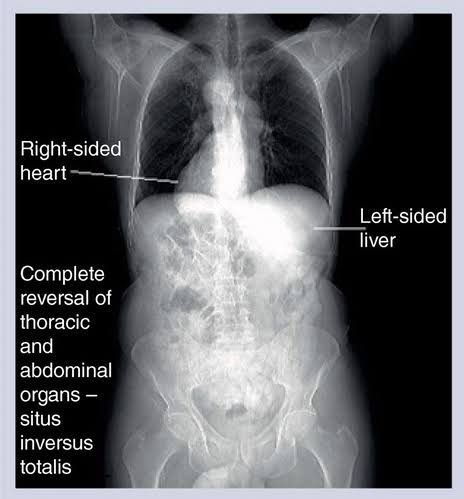

Situs inversus is a condition of the body where the internal organs of the body is reversed. It is a rare condition that is usually harmless but some may be associated with congenital anomalies and cardiac problems Picture credit: https://www.futuremedicine.com/doi/10.2217/fon.13.23